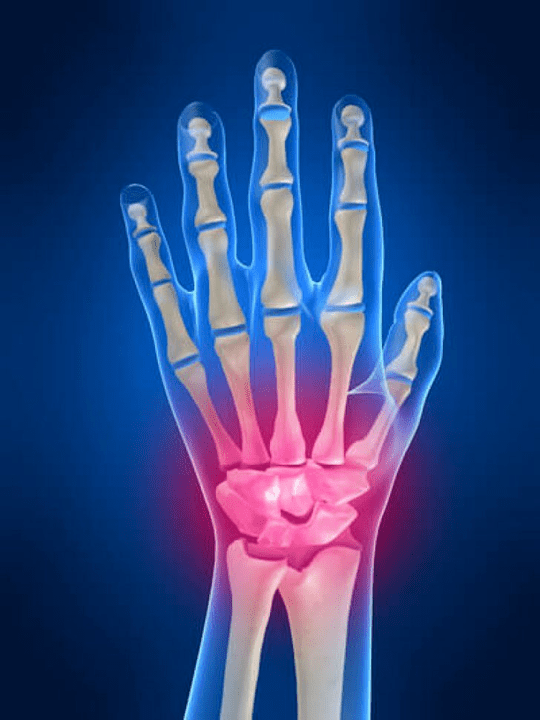

Douleurs articulaires Les doigts sont un signe indispensable de toute pathologie articulaire dans laquelle les composantes structurelles de ces articulations sont endommagées. Tout d'abord, la douleur dans le domaine de ces articulations peut être associée à diverses maladies auto-immunes (Un lustre rouge systémique, la polyarthrite rhumatoïde, l'arthrite psoriasique, etc.) dans lequel les facteurs immunitaires causent des dommages à leurs propres tissus articulaires.

La principale raison suivante qui peut initier douleur Dans les articulations des doigts, il peut y avoir des blessures (ecchymoses, luxations, fractures osseuses, ligaments). La douleur dans ces articulations peut également être provoquée par des changements dégénératifs survenant dans leurs tissus articulaires. Cela peut souvent être observé avec l'arthrose.

L'articulation du poignet

L'articulation du poignet est formée par les os des os proximaux (supérieur) un certain nombre de poignets (Trièdre, semi-lune, os scaphoïdes) et les zones distales de rayonnement et d'os des coudes. L'os du coude n'est pas directement connecté aux os du poignet, mais à l'aide de distal (Inférieur) le disque articulaire. Cette structure sépare la cavité de l'articulation du poignet de la cavité distale (Inférieur) L'articulation des carreaux.